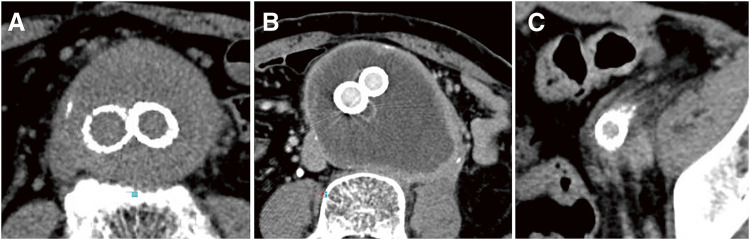

Objectives: Peri-aortitis following endovascular aneurysm repair (EVAR) is a rare phenomenon with unclear pathogenesis. In this study, we investigated its clinical features and sac prognosis. Methods: A retrospective analysis was conducted on 1369 EVAR. Peri-aortitis was defined using post-EVAR computed tomography. Clinical and imaging data were assessed. Results: Peri-aortitis following EVAR was identified in 12 patients (0.89%) with a mean age of 74 ± 8.9 years; 83.3% were male, and 41.7% had allergic or autoimmune histories. There were eight symptomatic cases (66.7%), including seven with fever, three with back or abdominal pain, and one with hydronephrosis. Precautionary antibiotic treatment was administered in five febrile cases. Although persistent and recurrent inflammation was observed in two cases (16.7%) each, inflammation resolved spontaneously in seven patients (58.3%). One (8.3%) needed steroid therapy for severe back pain. Aneurysm shrinkage was observed in seven cases (58.3%), while enlargement was noted in one case (8.3%) with type II endoleak. No correlation was found between aneurysm growth and peri-aortitis development. Conclusions: Peri-aortitis following EVAR may present significant challenges, including differentiation from infection, management of symptomatic cases requiring medical therapy, and addressing recurrences. Accurate diagnosis, individualized treatment, and meticulous follow-up are essential for favorable outcomes.